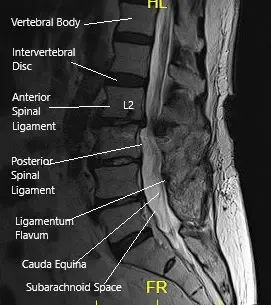

MRI of the LS spine in sagittal section.

CT scan signs of early screw loosening are seen. However, signs of bony ankylosis from L3-5 are also present. Degenerative spinal stenosis at L2-3 was present and was relatively unchanged since the most recent prior exam in 2018 but demonstrates progressive stenosis over the sequence of scans. MRI showed adjacent segment disease at L2-3 and L5-S1 with nerve root compressions.